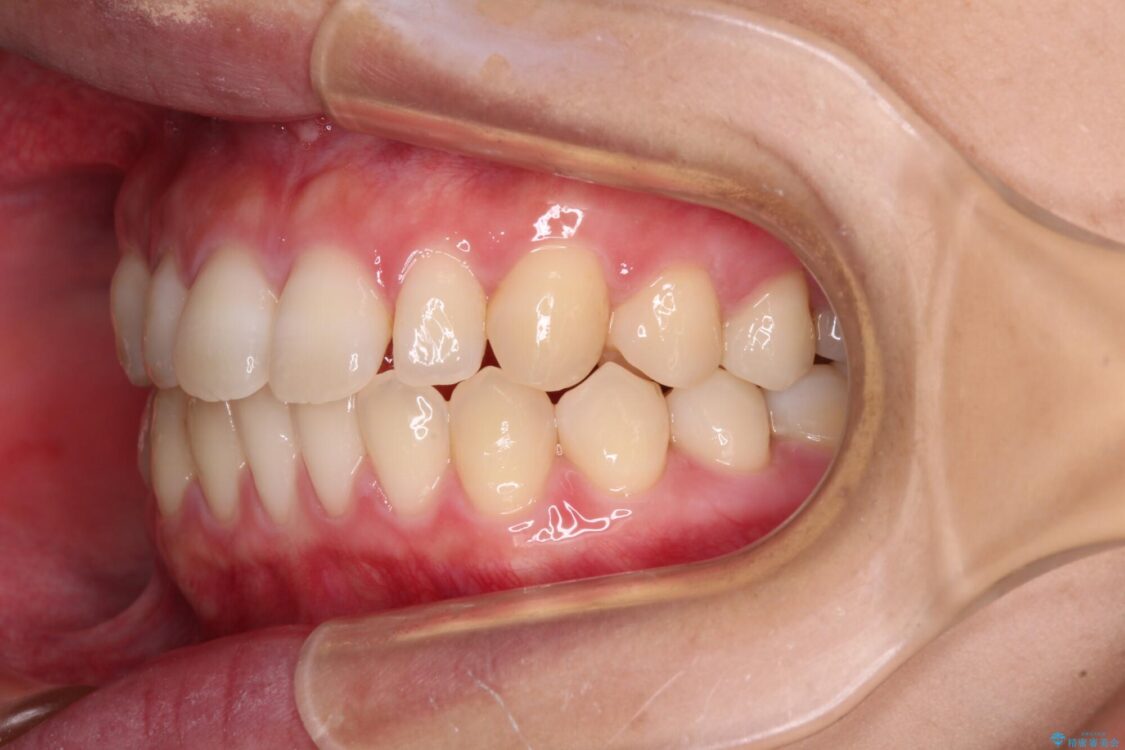

治療後

• 隙間だらけの歯列 インビザラインで改善 治療後画像